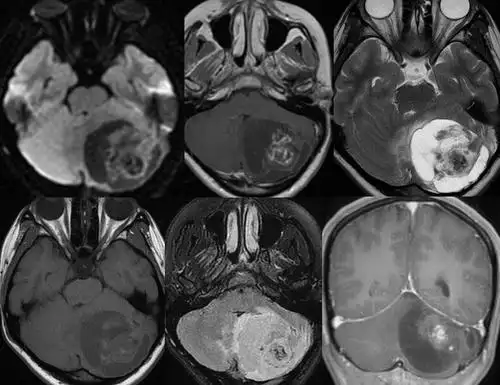

毛细胞性星形细胞瘤

毛细胞型星形细胞瘤,多形性黄色星形细胞瘤,室管膜下巨细胞星形细胞瘤